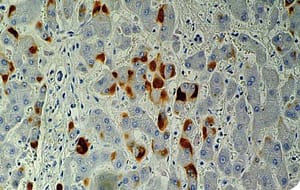

Fases de cronicidad de la hepatitis B

La primera fase de la infección crónica por el virus de la hepatitis B es la fase inmunotolerante, habitualmente en pacientes niños o jóvenes que se infectan, cursan con HBeAg positiva, antígenos de superficie positivo, cargas virales habitualmente altas, con transaminasas normales y sin impacto histológico en el hígado.

Hay una fase posterior replicativa en el adulto inmunocompetente que se infectó y se hizo crónico donde se encuentran cargas virales moderadas a altas, pero tienen alto impacto de inflamación hepática (por una situación inmunológica) y son pacientes que requieren tratamiento antiviral. Por lo general tienen antígeno de superficie positivo, transaminasas elevadas y biopsia que demuestra actividad inflamatoria.

Posteriormente se encuentra la fase de portador inactivo; estos son pacientes que mediante su inmunidad logran controlar la infección y mantener cargas virales muy bajas, con transaminasas normales, periodo que puede mantenerse por muchos años sin necesidad de tratamiento.

Por último existe la posibilidad de reactivación con cepas mutantes de promotor core y son la forma antígeno e negativo, que también vuelve a tener actividad inflamatoria con transaminasas elevadas y que requiere tratamiento antiviral.

Los dos grupos que tienen transaminasas elevadas (fase replicativa y fase de reactivación) requieren tratamiento.